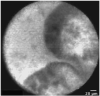

Results: Earlier published criteria were used to evaluate possible malignancy in the confocal images obtained in the 14 patients. None of the individual criteria were found to be specific enough for malignancy, but a normal-appearing reticular pattern without other putative markers of malignancy was observed in all normal patients. Multiphoton reconstructions of intact rat bile ducts revealed that the reticular pattern seen in normal tissue was in the same focal plane but was smaller than blood vessels. Special stains identified the smaller structures in this network as lymphatics.

Conclusions: Our limited series suggests that a negative confocal imaging study of the biliary tree can be used to rule out carcinoma, but there are frequent false positives using individual earlier published criteria. An abnormal reticular network, which may reflect changes in lymphatics, was never seen in benign strictures. Better correlation with known histologic structures may lead to improved accuracy of diagnoses.